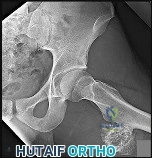

A 72-year-old female falls and sustains a displaced, intracapsular femoral neck fracture. Due to the high risk of avascular necrosis and nonunion associated with this injury pattern, a hemiarthroplasty is planned. The profound vascular vulnerability of the adult femoral head is due to its heavy reliance on the ascending cervical branches. Which artery is the primary source of these critical ascending branches?

Correct Answer: Medial femoral circumflex artery

Explanation:

In the adult, the principal blood supply to the femoral head is derived from the medial femoral circumflex artery (MFCA). The MFCA gives rise to the lateral epiphyseal artery system (ascending cervical branches) that penetrate the joint capsule at the base of the femoral neck and course along the retinaculum to perfuse the femoral head. Displaced intracapsular fractures disrupt these vessels, leading to a high rate of osteonecrosis. The artery of the ligamentum teres provides a negligible supply in adults.